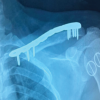

Excision of fungating soft tissue with curettage with cementing was done (Figs. 4 and 5).

ABC is a lesion that usually occurs in the metaphysis of long bones, mainly the load-bearing ones. ABC can occur either as a primary or secondary lesion, for example, related with chondroblastoma or osteoblastoma. ABCs have a destructive and aggressive nature due to which apart from the metaphysis, physis of the bone also gets involved resulting to disturbances in growth plate and development of deformities [4]. ABC appears as a lytic and expansile lesion radiographically with septae and cortical thinning showing fluid-fluid levels on MRI, also observed in our case. Optimal treatment of ABC is arguable. In spite of several techniques reported in literature, the recurrence rate of ABCs lies anywhere between 5% and 40%, sometimes greater than that [5]. Even though newer techniques such as sclerotherapy (that uses sclerosing substances) and synthetic bone grafts have come into play, still they remain less effective in comparison to the conventional curettage method [6]. At present, curettage and packing the void with bone graft or polymethyl methacrylate are the cornerstone of treatment strategy [6]. Curettaging giant ABCs usually leave large defects which are difficult to treat. To reconstruct these large defects, multiple reconstructive alternatives such as autografts, allografts, and bone substitutes are available [7]. Amongst these, autografts are comparatively easier to incorporate than allografts as allografts experience a low-grade immune response and lack of osteocytes or both [8]. Recently, vascularized bone grafts have come into the picture as a treatment modality for large bone defects as they can be remodeled and incorporated faster; however, this is a challenging process [9]. Our choice was to use bone cement as they provide excellent structural bone support and are technically uncomplicated to use. Furthermore, literature shows brilliant long-term results of bone cementing [10]. In our patient, the final construct obtained was firm and allowed gradual weight-bearing without failure (Fig. 6 and 7). Post-operative clinical pictures and radiograph post 6-month follow-up are shown in Fig. 8 and 9.